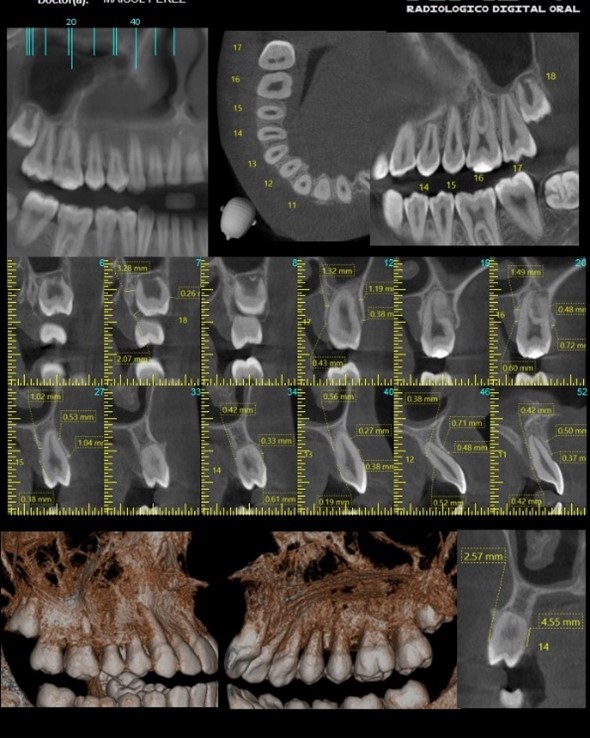

El dentista podrá hacer en el ordenador cortes bi y tridimensionales de las imágenes que obtiene. Le permitirá observar con detalle cualquier característica de la boca del paciente como:

- La densidad y calidad del hueso.

- Por donde pasan los vasos sanguíneos y nervios.

- El TAC dental asegura una buena precisión para diseñar el plan de tratamiento odontológico más adecuado.

- Presenta un gran avance con respecto a las radiografías panorámicas (ortopantomografías) convencionales.